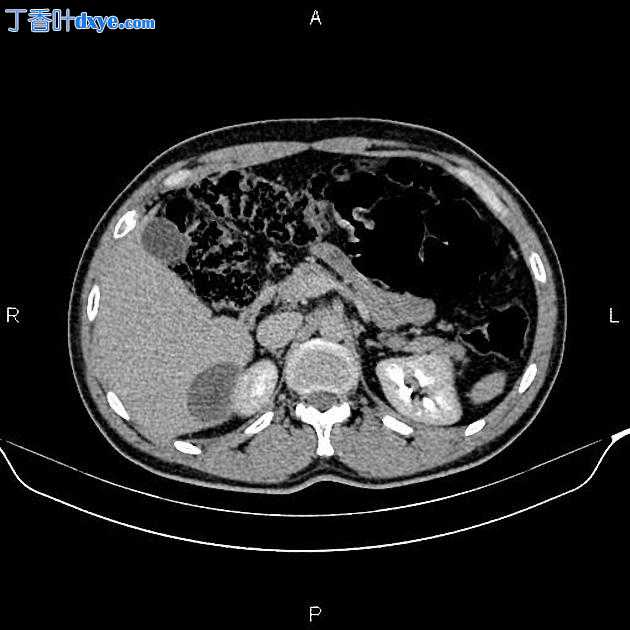

2.jpeg

Axial C+ arterial phase

在右肝叶小于 55 mm 处可见三个相邻的厚壁囊性病变。

此外,还描绘了一个直径为 15 毫米的低密度肝病灶,位于第 4 肝段(Couinaud 的命名法),显示早期外周、结节状强化和向心性充盈。特征与血管瘤最相容。